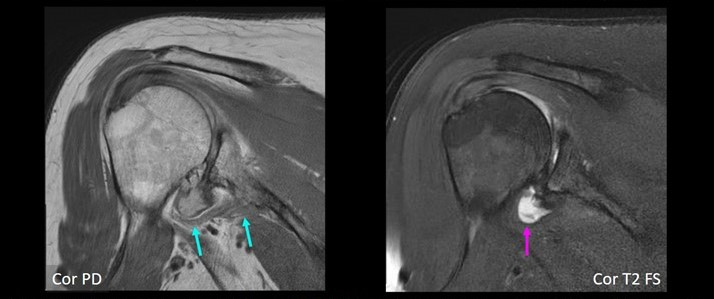

66-year-old female with severe shoulder pain. Coronal MR images show definite small AIGM (blue arrows), corresponding to diagnostic confidence of 4. In addition, there is high-grade glenohumeral osteoarthrosis, as well as small joint effusion (purple arrow).